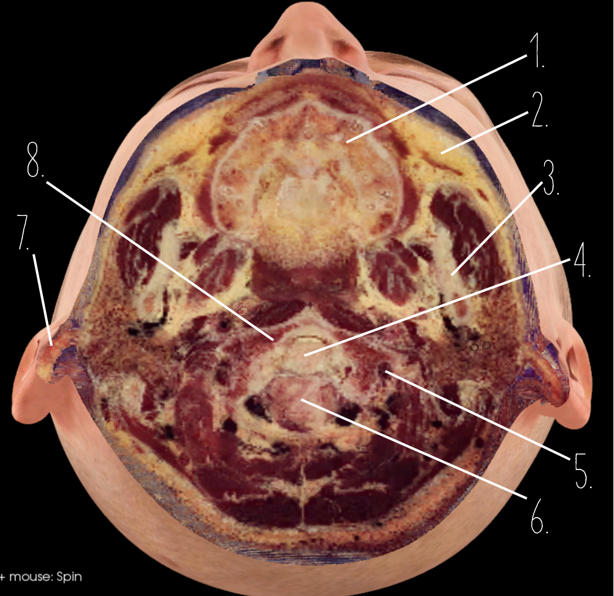

1?

Nasal Bone

2?

Maxillary Sinus

3?

External Acoustic Meatus

4?

Pons

5?

Cerebellum

6?

Mastoid Air Cells

7?

Mandibular Condyles

8?

Sphenoid Bone

9?

Maxillary Bone